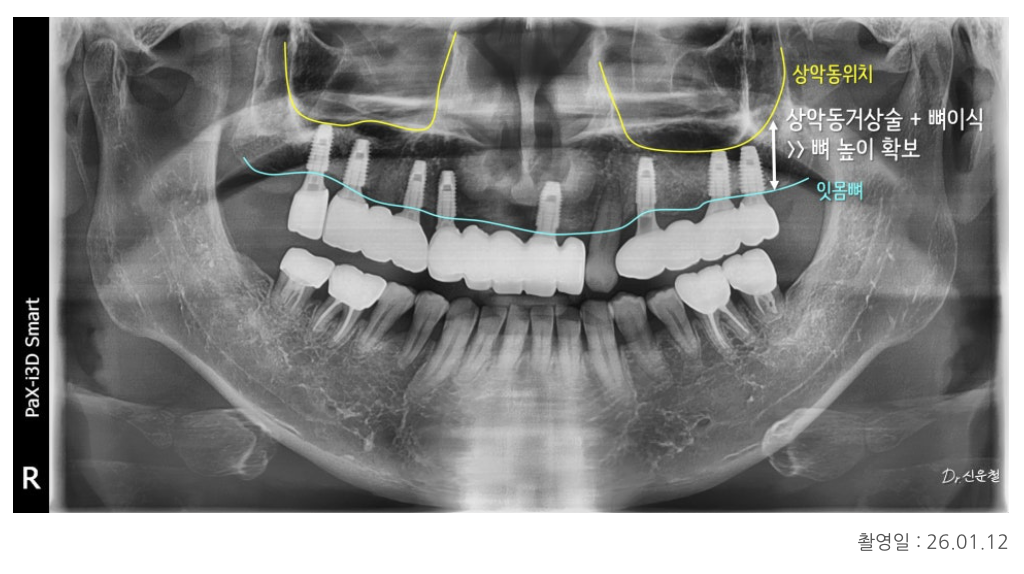

상악동 거상술을 통한 기초 치료

위턱 어금니 부위는

오래전 치아를 상실해 임플란트를 바로 심기엔 뼈 높이가 부족했습니다.

그래서 먼저

상악동 거상술을 통해

위턱 안쪽 공간을 들어 올리고

임플란트를 지지할 수 있는 뼈를 보강한 뒤

단계적으로 임플란트 치료를 진행했습니다.